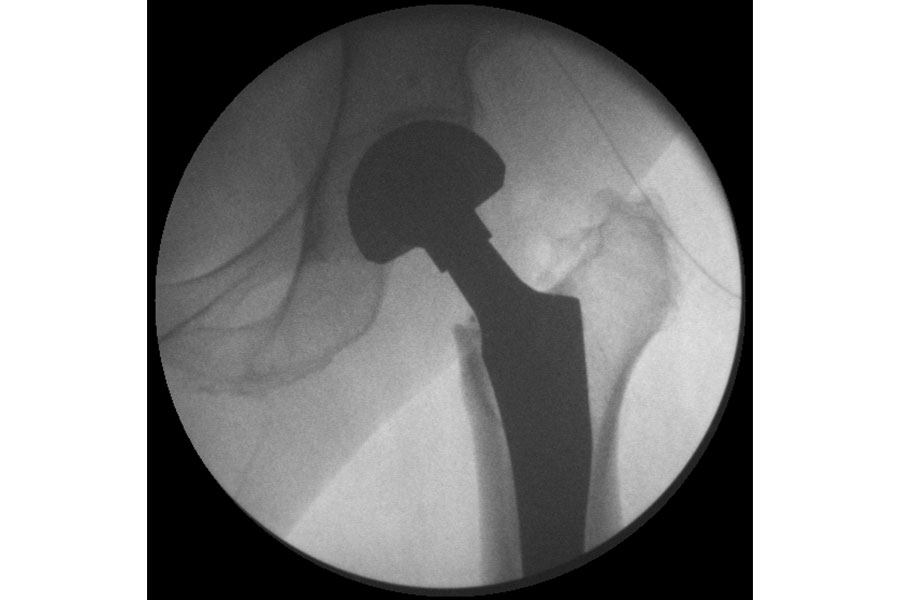

Total Hip Replacement

Case 1